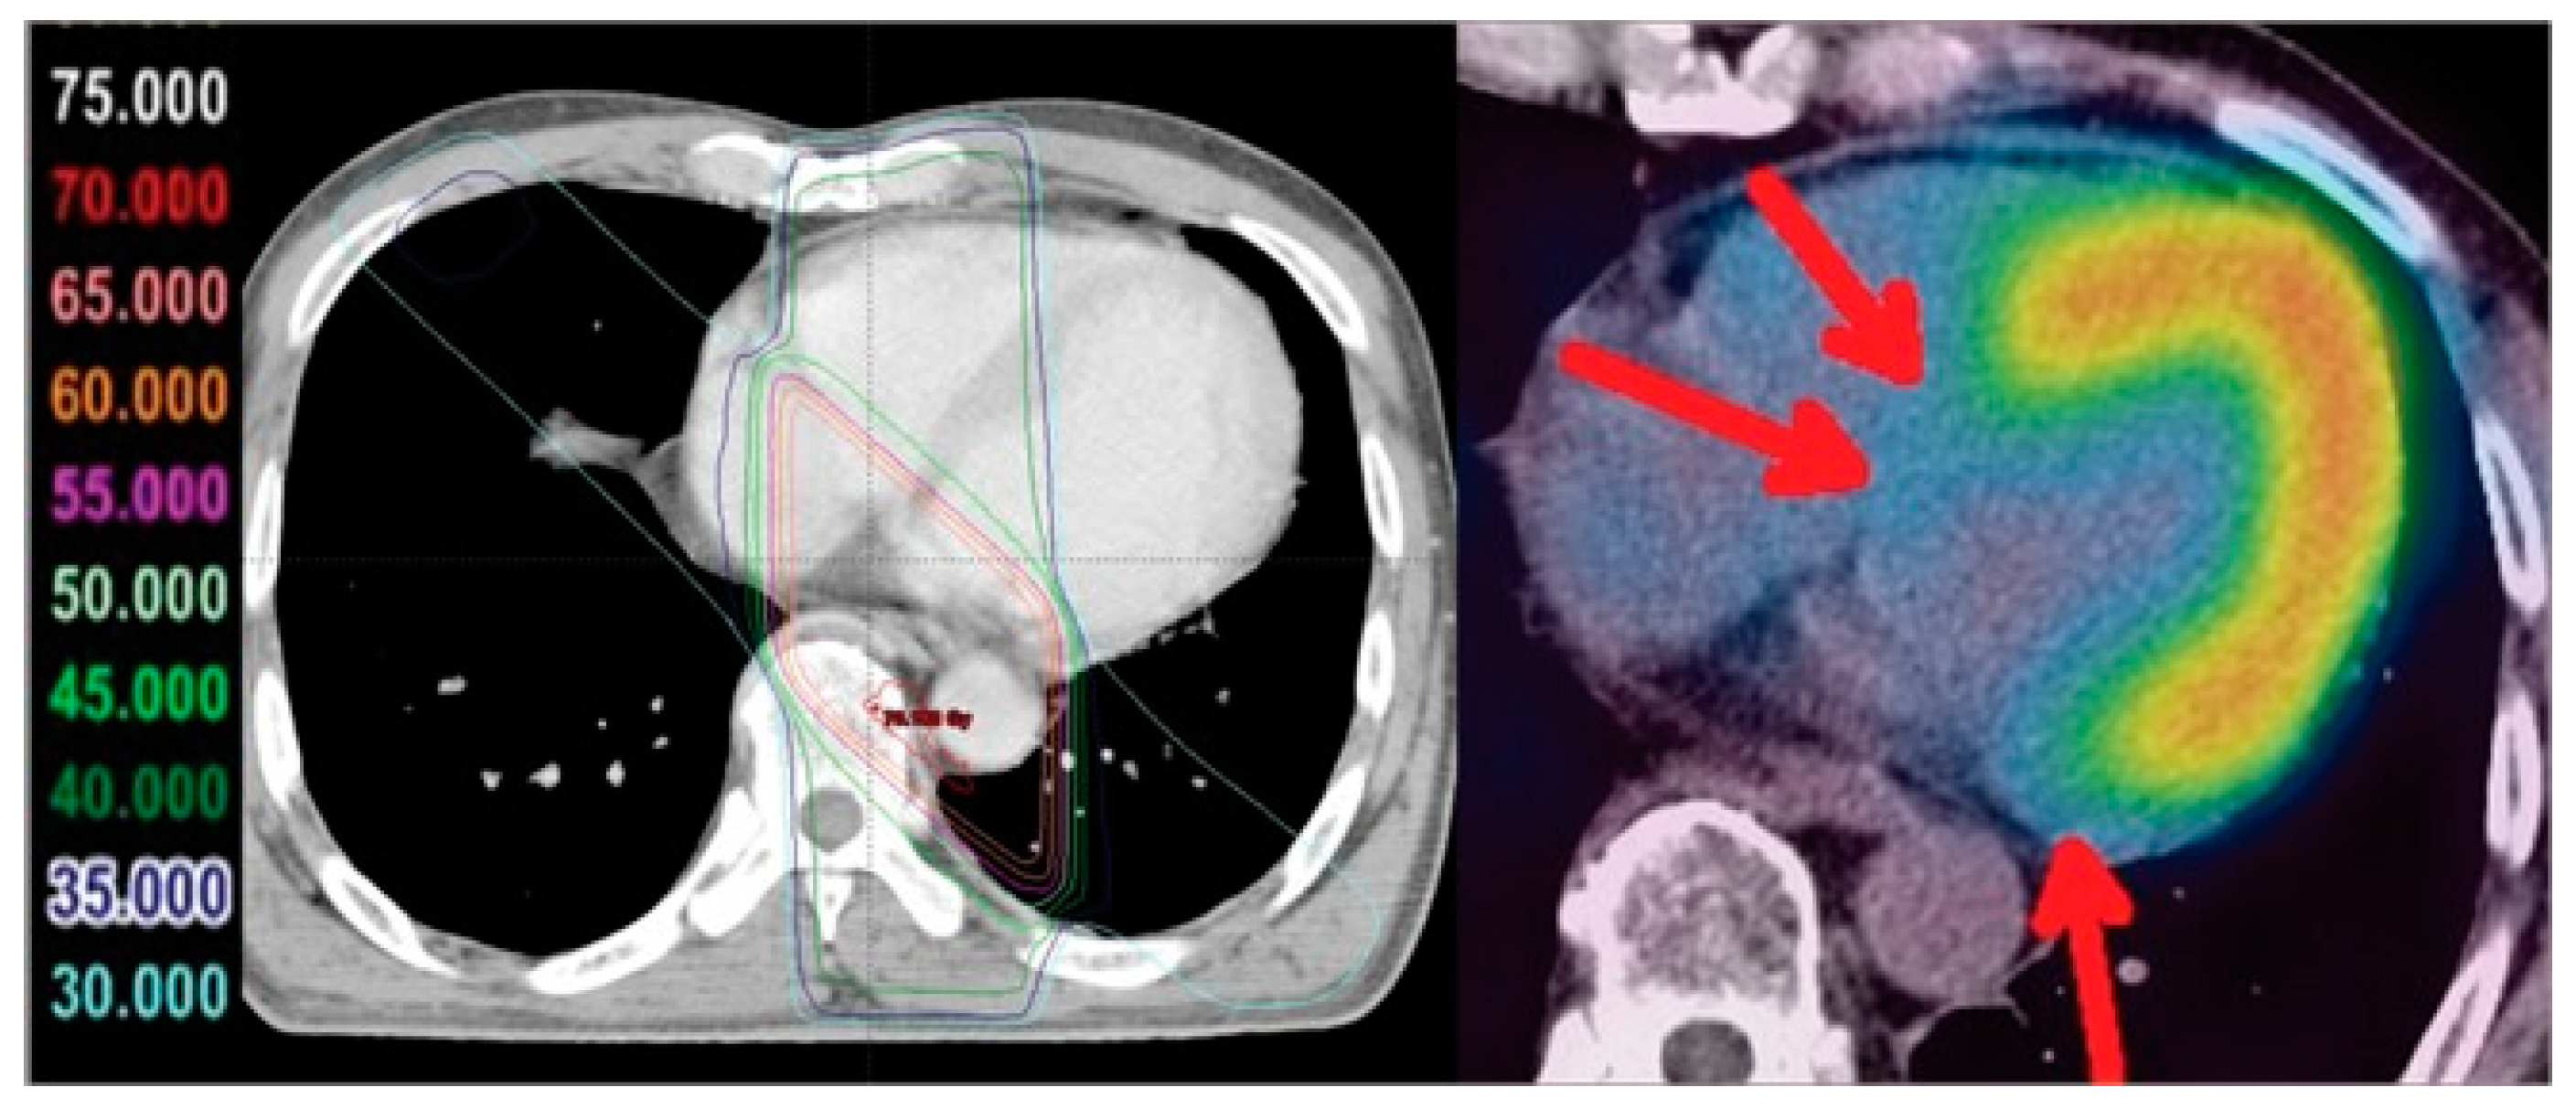

- Jingu, K.; Kaneta, T.; Nemoto, K.; Ichinose, A.; Oikawa, M.; Takai, Y.; Ogawa, Y.; Nakata, E.; Sakayauchi, T.; Takai, K.; et al. The utility of 18F-fluorodeoxyglucose positron emission tomography for early diagnosis of radiation-induced myocardial damage. Int J Radiat Oncol Biol Phys 2006, 66, 845–851. [Google Scholar] [CrossRef] [PubMed]

- Gorla, A.K.; Sood, A.; Prakash, G.; Parmar, M.; Mittal, B.R. Substantial Increase in Myocardial FDG Uptake on Interim PET/CT May Be an Early Sign of Adriamycin-Induced Cardiotoxicity. Clin Nucl Med 2016, 41, 462–463. [Google Scholar] [CrossRef] [PubMed]